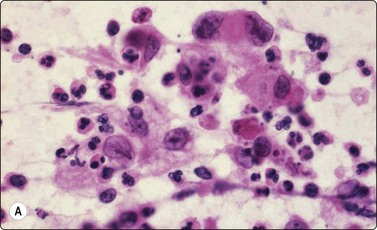

Merkel cell carcinoma (neuroendocrine carcinoma of skin) (Fig. 14.17, and see Fig. 5.23)61,62

image

Fig. 14.17 Merkel cell carcinoma

(A) Poorly cohesive cells; nuclear pleomorphism and some molding, scanty blue cytoplasm resembling lymphoid cells (MGG, HP); (B) Cellular smear of dispersed small cells with round, dark nuclei (Pap, HP); (C) Dot-like positive staining with CAM5.2 (immunostaining, HP).

Criteria for diagnosis

Cell-rich smears of mainly dispersed small neoplastic cells,

Fragile, scanty, blue (MGG) cytoplasm; high nuclear : cytoplasmic ratio; many stripped nuclei,

Clustered cells may show nuclear molding and rosette-like grouping,

Round or ovoid, mildly to moderately irregular hyperchromatic nuclei with inconspicuous nucleoli,

Mitoses frequent,

Lymphoid globules (lymphoglandular bodies) absent,

Dot-like paranuclear staining for cytokeratin; chromogranin usually positive.

Primary neuroendocrine carcinoma of skin is an uncommon neoplasm, mainly seen in elderly patients and most often in the head and neck. It is locally aggressive and often metastasizes to regional lymph nodes. Clinically and cytologically, Merkel cell tumor can be difficult to distinguish from non-Hodgkin lymphoma when it presents as lymphadenopathy without an obvious primary, as is often the case (see Chapter 5).

Page 379

Smears are usually highly cellular. The cells are mainly dispersed but some are clustered or form single files with nuclear molding and sometimes rosette-like groups. The main differential diagnoses are lymphoma and metastatic small cell carcinoma. Amelanotic melanoma may also be considered. The absence of lymphoid globules in the background and subtle differences in nuclear chromatin help in this distinction. Staining for CAM5.2, CK7 and CK20 demonstrates characteristic dot-like intracytoplasmic deposits in the tumor cells (Fig. 14.17C), and staining for neuroendocrine markers is usually positive. Electron microscopy shows well-demarcated whorls of cytoplasmic filaments.